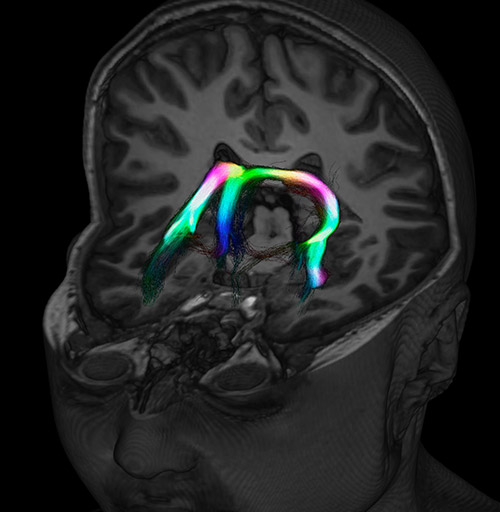

Fiber tracking from the left and right hippocampi to the fornix.

Fiber tracking from the left and right hippocampi to the fornix (green), and the corticospinal track based on a seed region of the posterior limb of the internal capsule.